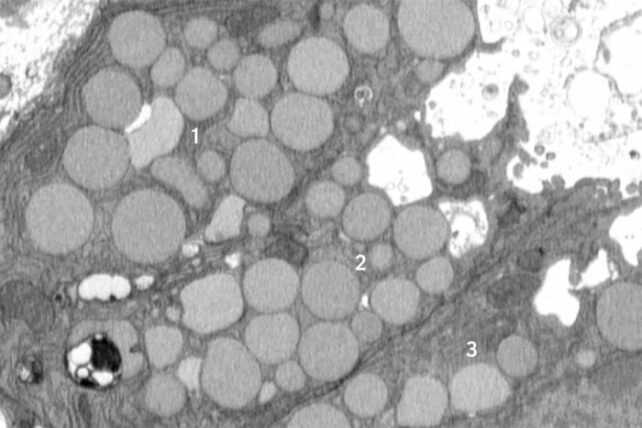

Injured Cells Can 'Vomit' Waste to Boost Healing, Study FindsThree mouse stomach cells (numbered 1-3) are shown jettisoning cellular debris through cavities (white) that form in their membranes. (Jeffrey Brown/Washington University School of Medicine)

Using a mouse model of stomach injury, Brown and his colleagues demonstrated the vomiting response is a standard behavior of cells in paligenosis, not just a quirk.